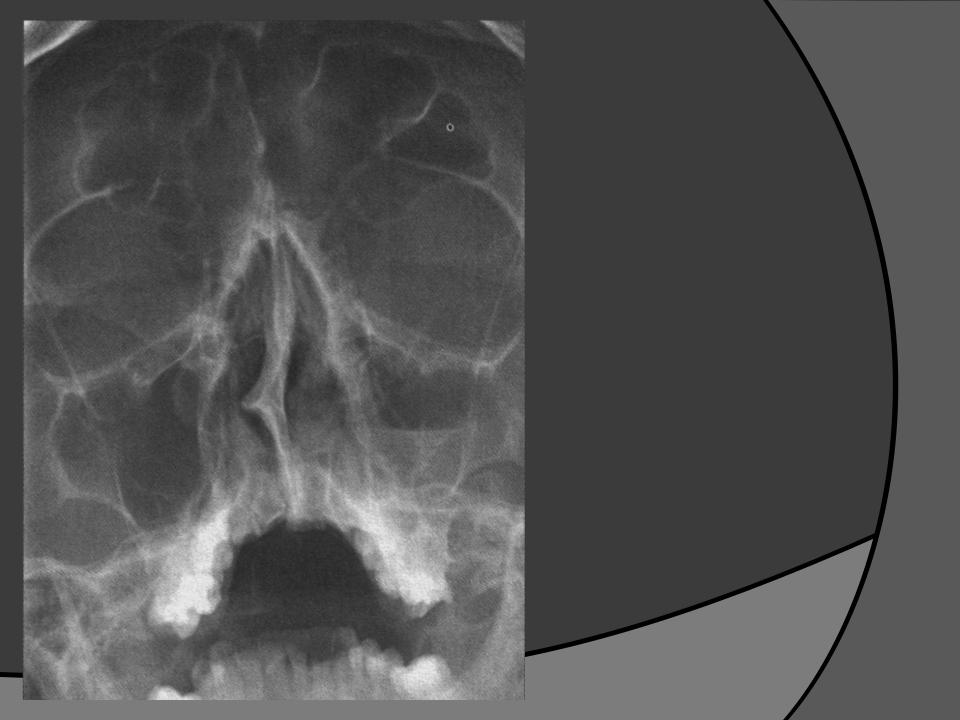

КТ-снимки хронического этмоидита: подробная визуализация